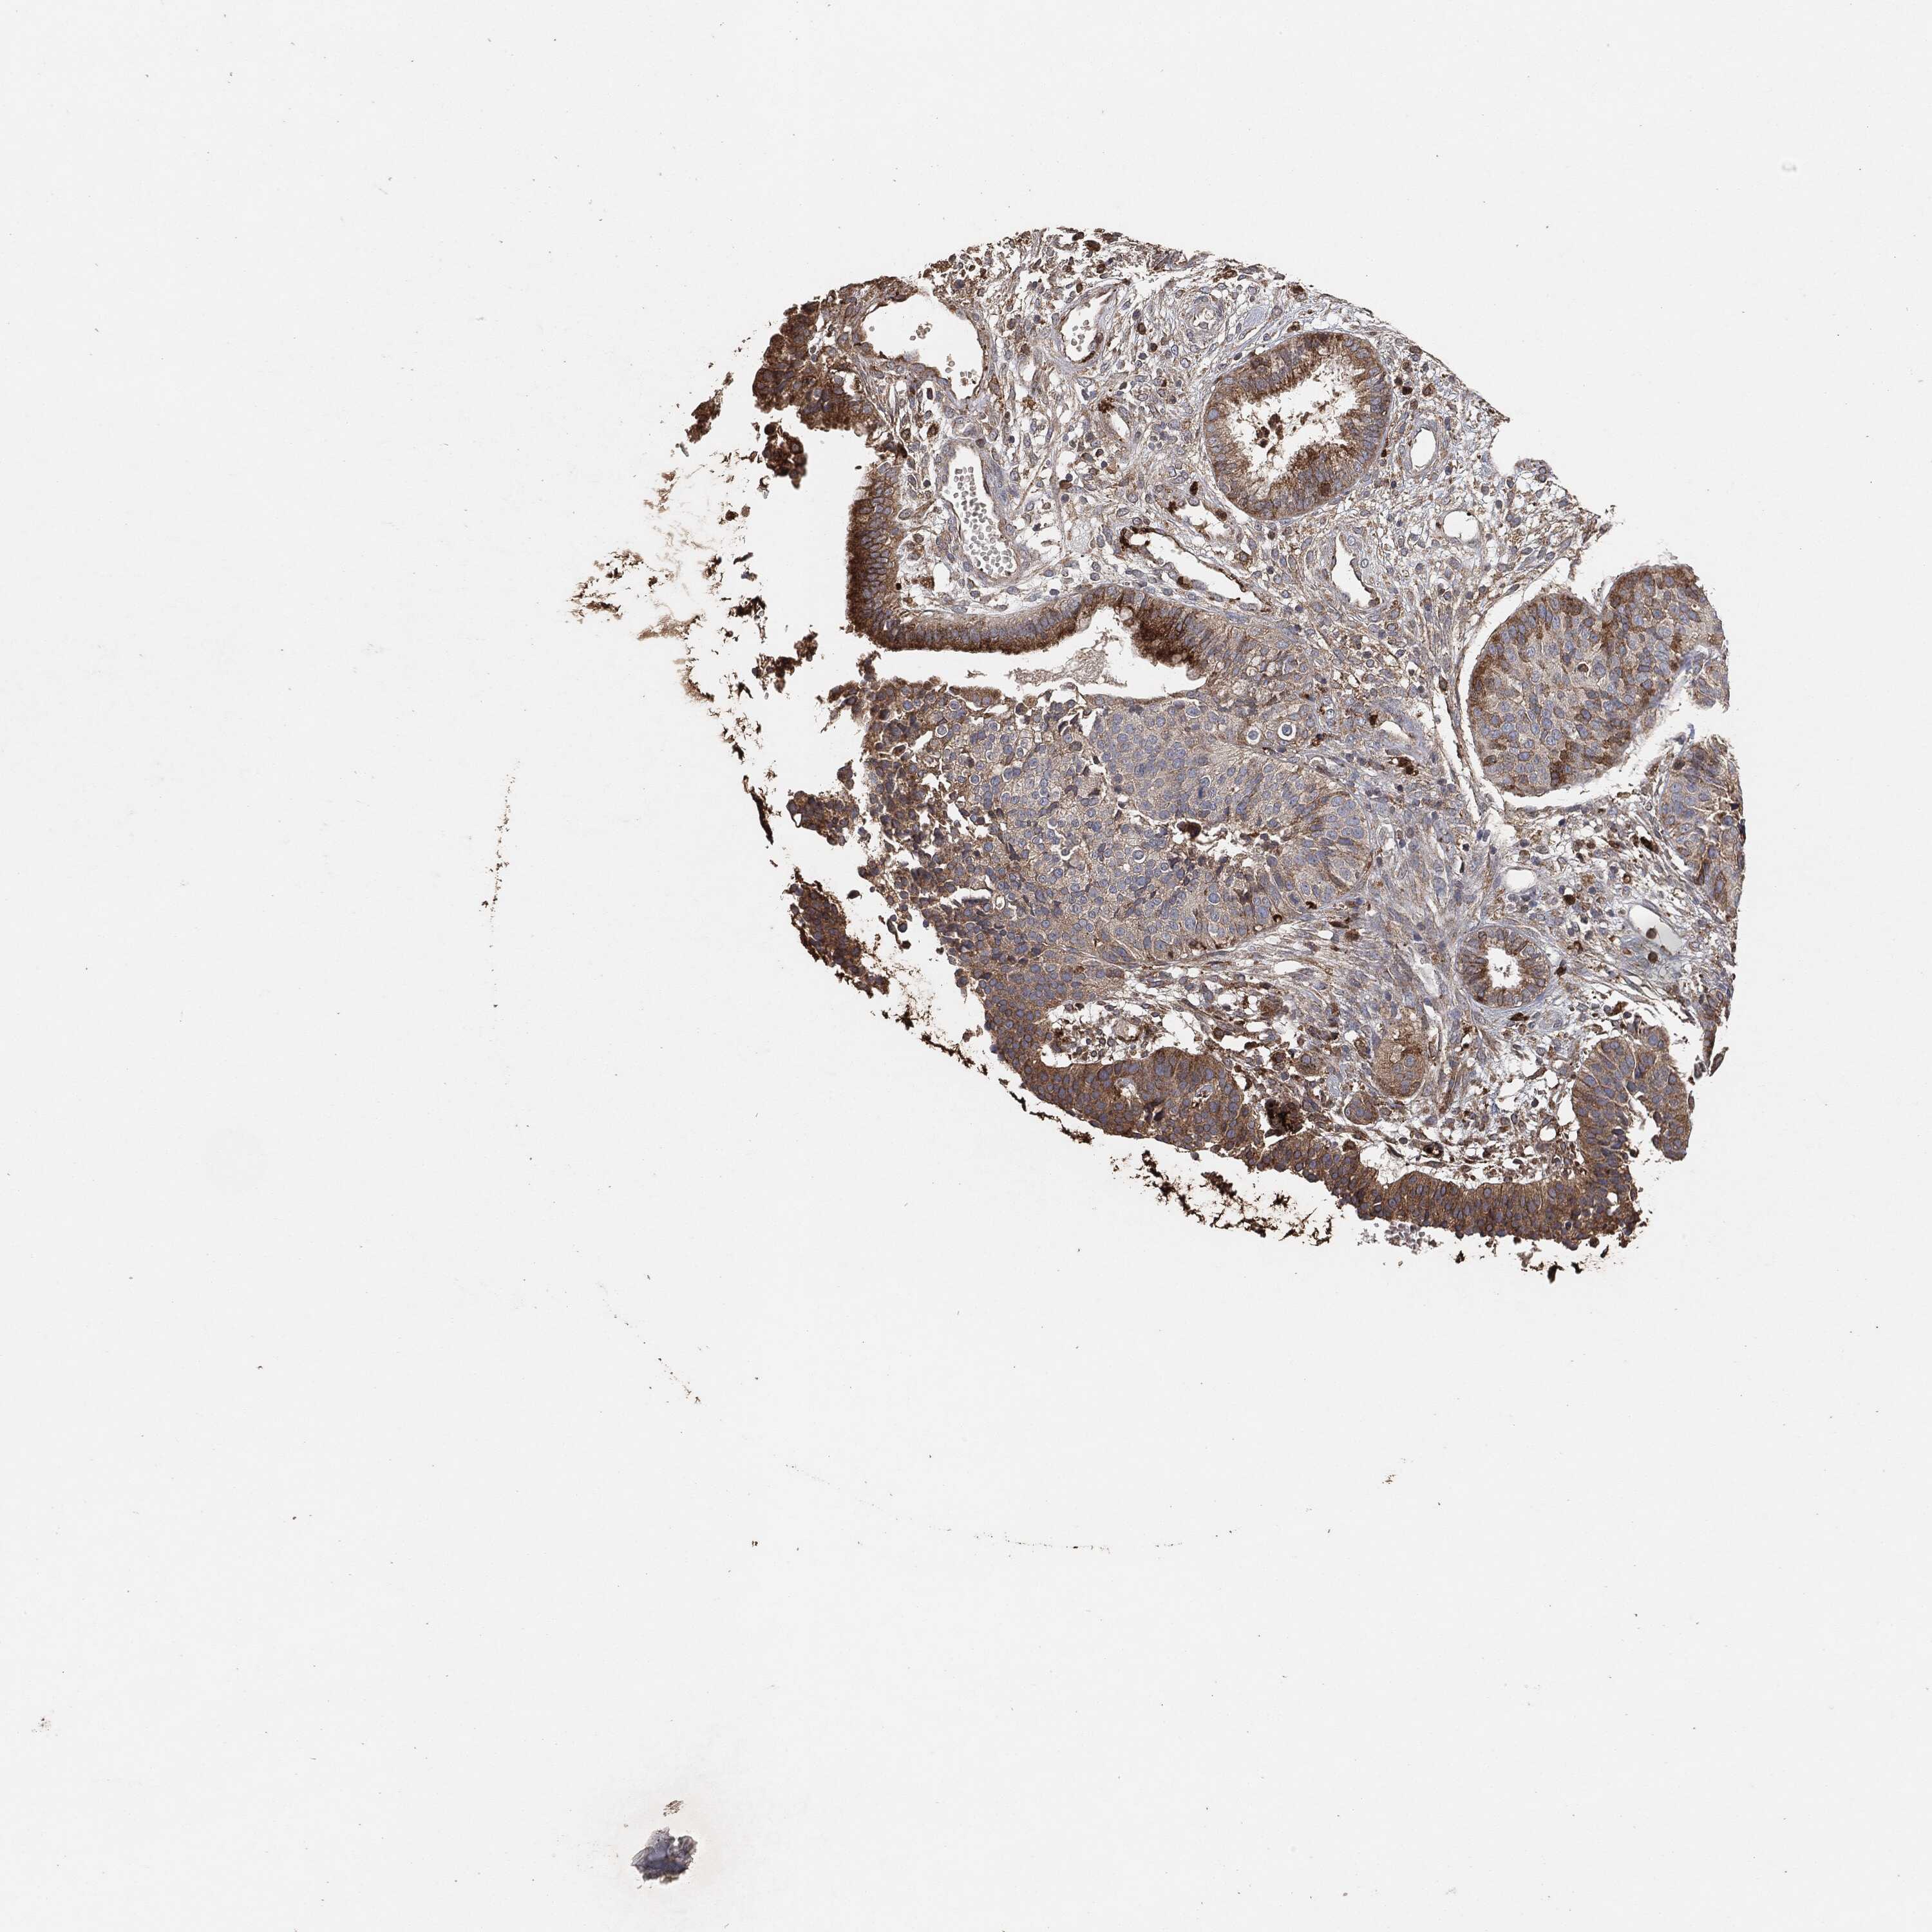

CERVICAL CANCER - Protein expressioni

A mouse-over function shows sample information and annotation data. Click on an image to view it in a full screen mode. Samples can be filtered based on level of antibody staining by selecting one or several of the following categories: high, medium, low and not detected. The assay and annotation is described here.

Note that samples used for immunohistochemistry by the Human Protein Atlas do not correspond to samples in the TCGA dataset.

Antibody stainingi

Antibody staining in the annotated cell types in the current human tissue is reported as not detected, low, medium, or high, based on conventional immunohistochemistry profiling in selected tissues. This score is based on the combination of the staining intensity and fraction of stained cells.

Each image is clickable and will lead to virtual microscopy that enables deeper exploration of all samples and also displays staining intensity scores, fraction scores and subcellular localization as well as patient and tissue information for each sample.

Staining

High

Medium

Low

Not detected

Intensity

Strong

Moderate

Weak

Negative

Quantity

>75%

75%-25%

<25%

None

Location

Nuclear

Cytoplasmic/membranous

Cytoplasmic/membranous,nuclear

Adenocarcinoma, NOS

Squamous cell carcinoma, NOS